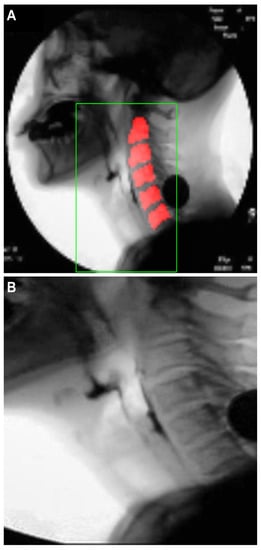

2.3.1. Creation of a Dynamic ROI Using Global Localization of the Cervical Spinal Column